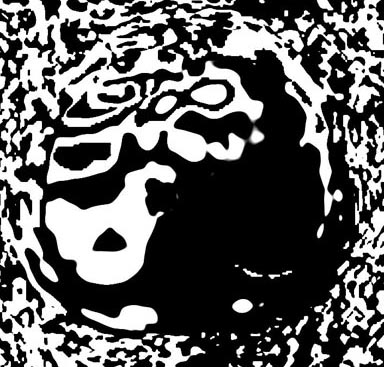

Figure 3. Grey Elastogram, no mask

Figure 4. Grey Elastogram, with mask